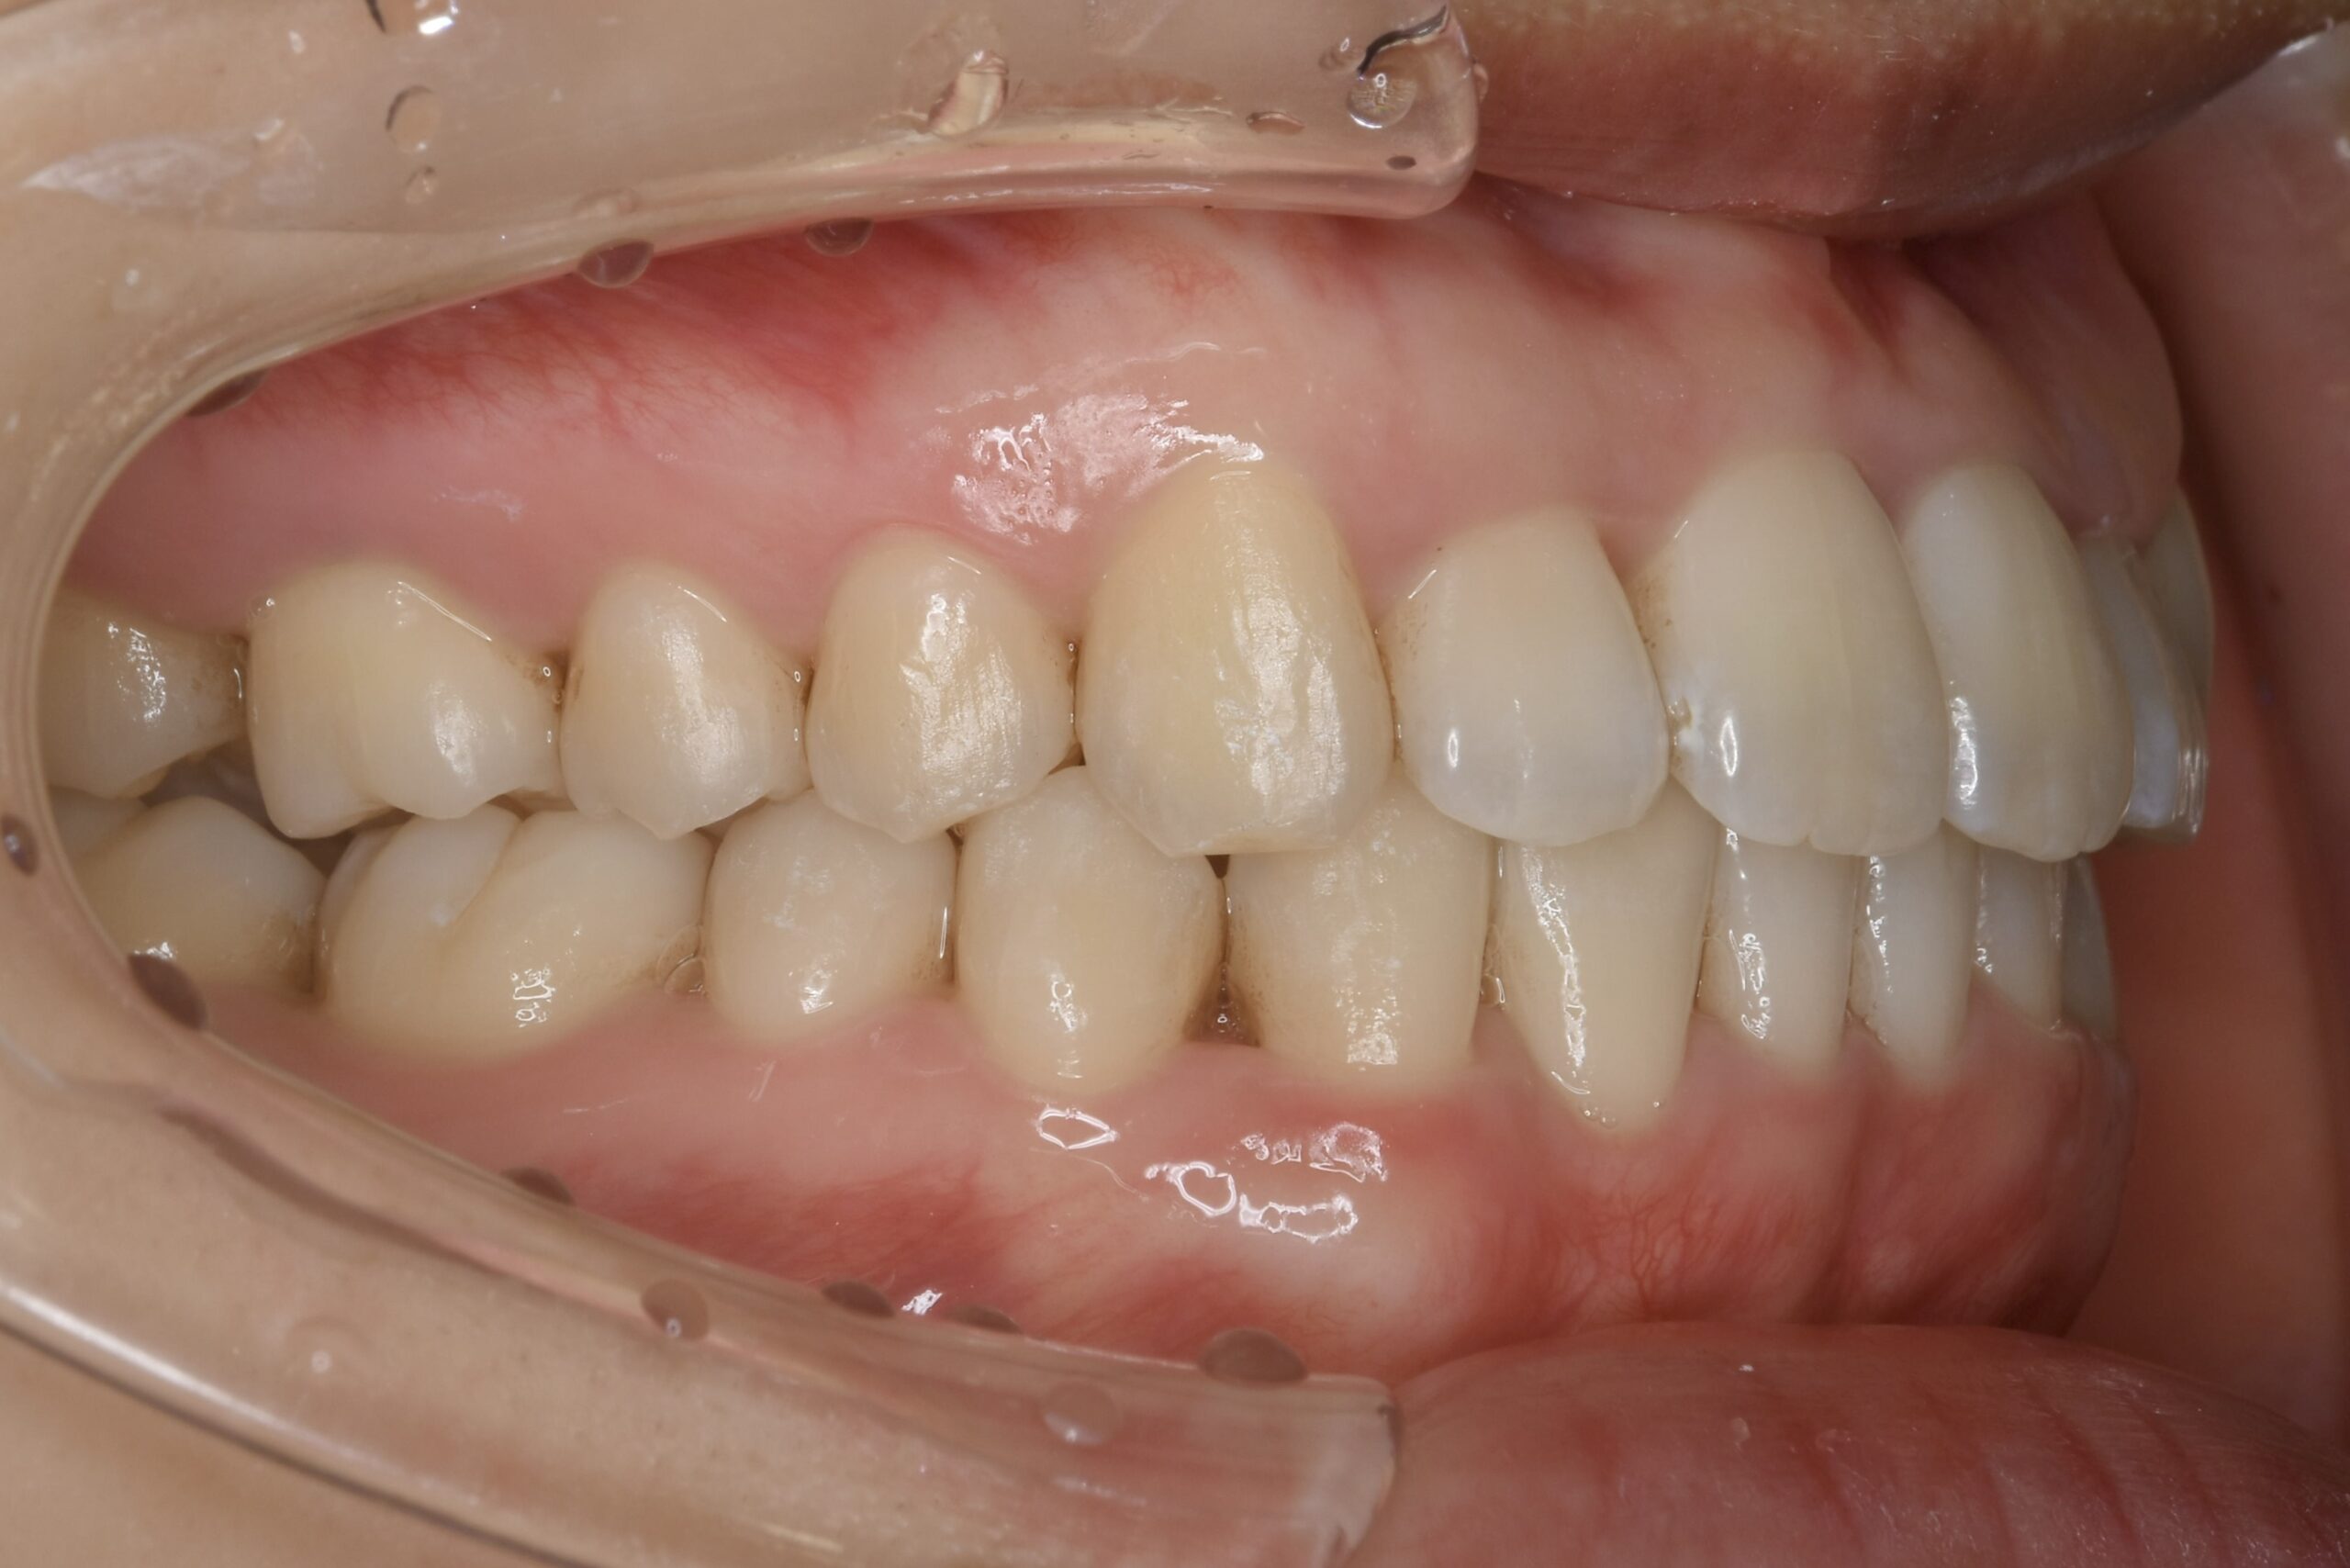

21歳 女性 治療期間:1年1ヶ月

叢生(ガタガタ)

マウスピース矯正装置(インビザライン)

BEFORE

AFTER

診断名・主な症状

叢生

治療内容

上下とも歯並びの横幅を広げながら、でこぼこを解消しました。

マウスピース矯正(インビザライン)

抜歯あり(智歯抜歯)

治療期間

1年1ヶ月